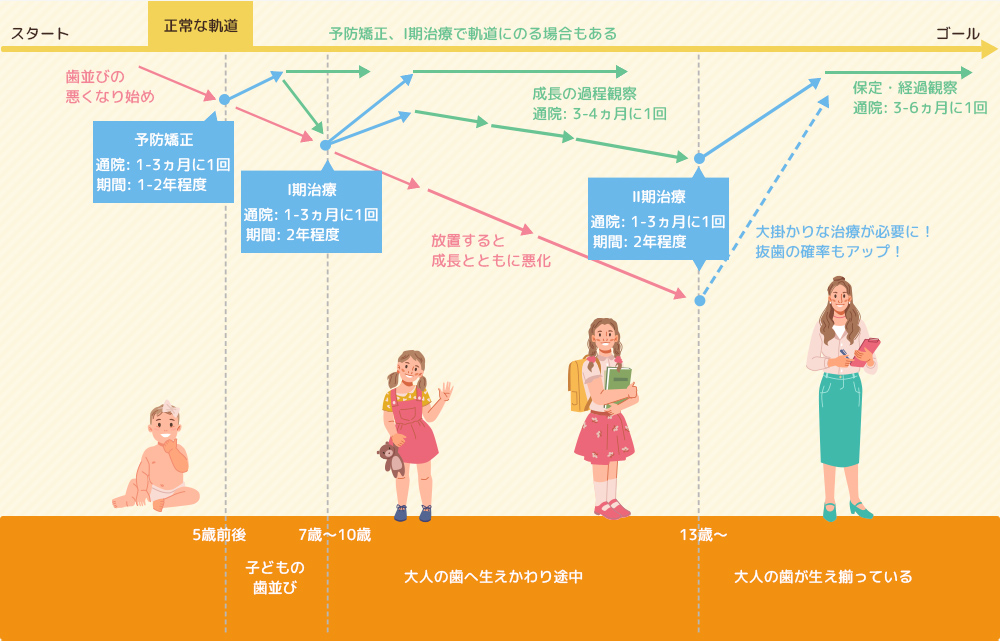

矯正を始める時期について

治療の流れ